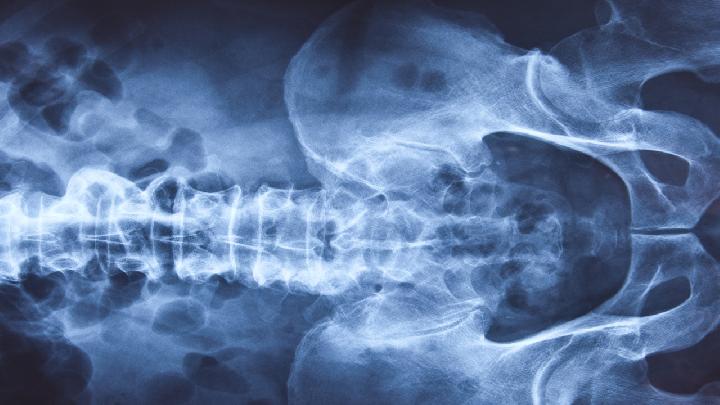

过去的B超设备只能检查胎儿的生理指标,而四维彩超还能对胎儿的体表进行检查,如唇裂,脊柱裂,大脑、肾、心脏、骨骼发育不良等,以便尽早的进行治疗。生个聪明健康的小宝宝,并且将宝宝的样子和动作制作成照片或VCD,让宝宝拥有最完整的0岁相册,这已经不再是幻想。